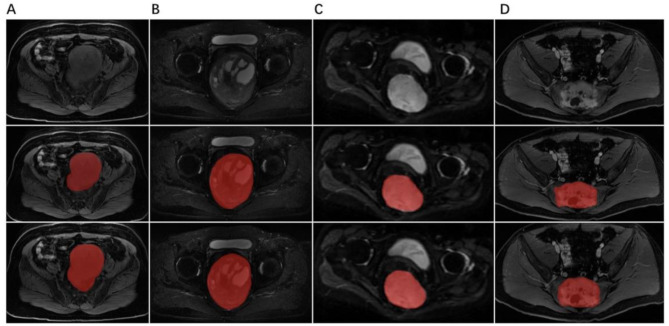

Materials and methods: This study included a total of 616 patients with pathologically confirmed PSTs between April 2011 to May 2022. We proposed a practical DL framework that integrates a 2.5D U-net and MobileNetV2 for automatic PST segmentation with a fast annotation strategy across multiple MRI sequences, including T1-weighted (T1-w), T2-weighted (T2-w), diffusion-weighted imaging (DWI), and contrast-enhanced T1-weighted (CET1-w). Two distinct models, the All-sequence segmentation model and the T2-fusion segmentation model, were developed. During the implementation of our DL models, all regions of interest (ROIs) in the training set were coarse labeled, and ROIs in the test set were fine labeled. Dice score and intersection over union (IoU) were used to evaluate model performance.

Results: The 2.5D MobileNetV2 architecture demonstrated improved segmentation performance compared to 2D and 3D U-Net models, with a Dice score of 0.741 and an IoU of 0.615. The All-sequence model, which was trained using a fusion of four MRI sequences (T1-w, CET1-w, T2-w, and DWI), exhibited superior performance with Dice scores of 0.659 for T1-w, 0.763 for CET1-w, 0.819 for T2-w, and 0.723 for DWI as inputs. In contrast, the T2-fusion segmentation model, which used T2-w and CET1-w sequences as inputs, achieved a Dice score of 0.833 and an IoU value of 0.719.